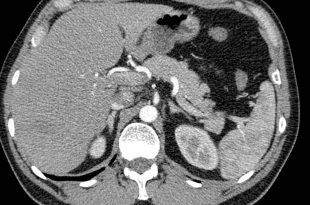

Если опухоль формируется клетками, подобными  структуре паренхимы, сосудов или желчеточных протоков печени, говорят о доброкачественности. Особенности — медленный рост, редкость появления, отсутствие метастаз. Симптомы в виде тошноты, отрыжки воздухом, желтухи, боли в межреберье возникают при значительном увеличении и сдавливании ближайших органов. Диагноза ставится УЗИ, КТ, коагулограмме, биопсии. Причины до конца не изучены, роль провокаторов еще не доказана. Чаще — это плохая экология, питание, генетика и вредные привычки. Бессимптомные опухоли наблюдаются, остальные — удаляются. Прогноз — благоприятный.